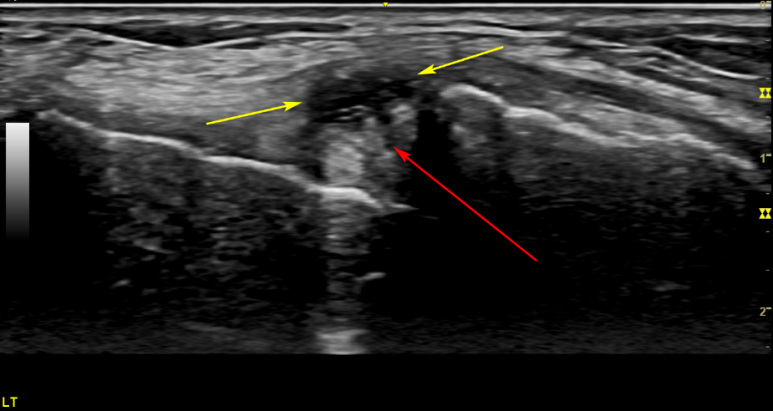

치료 전

8개월 치료 후

8개월 치료 후에음곡혈에서 촬영한경혈 초음파 영상**입니다.

연골 파열로 인한 반월판 낭종(노란색 화살표)이

변화된 것이 보이시나요??

특히 저 물혹을 눌러보면 아주 심한 통증이 나타났는데, 뽑아보니 아주 끈끈한 젤라틱 점액이 꽉 차있었습니다.

최근 들어 악화된 통증은 반월판 낭종이 주변 조직을 압박하면서 생겼을 가능성이 있었습니다.